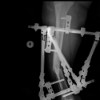

One stage deformity correction by RLF external fixator followed by TTC nail for chronic stage Charcot ankle and hindfoot neuroarthropathy

Surgical treatment of the chronic stage (Eichenholtz stage3) of the Charcot neuroarthropathy of ankle is extremely challenging, especially for those with disappearing talus (Dounis type III). In the present study, we present a new surgical technique to treat this difficult condition. The surgery involved a small anterolateral incision centered lateral malleolus, distal fibular osteotomy to mobilize the distal fibular as vascularized bone graft for reconstruction of the talus bone defect. The same incision was used for tibia-talus and sub-talus joint preparation by removing of cartilage till bleeding bone. A small medial incision over talus-navicular was also made for joint preparation and fixation. A pre-assembled Styker LRF circular external fixator was then applied across the ankle joint. Gross deformity was corrected by traction via unlocked telescopic struts. The fine tone correction was achieved by push/pull technique using additional pin or turning locked struts. Once deformity correction was satisfied. a guide pin was then inserted through calcaneus, talus and the distal tibia to hold the position. The TTC nail was then inserted as usual. The circular external fixator was removed after medullary canal preparation. Additional screw may be added to secure the fixation of the distal fibular to the distal tibia or talus. Our technique combines the advantage of ring fixator deformity correction without extensive dissection and adequate compression plus secure fixation of TTC nail for ankle and hind foot fusion for Charcot ankle. It is safe and effective with minimal bony work and soft tissue release, which leads to less complications.